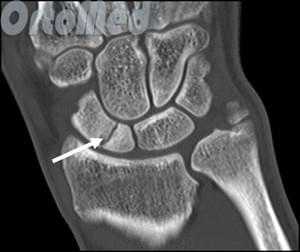

Диагностика переломов ладьевидной кости

Очень важно диагностировать перелом ладьевидной кости как можно раньше, поскольку значительная часть ладьевидной кости имеет плохое кровоснабжение и перелом может не срастись, или наступить некроз фрагмента кости (некровоснабжаемый фрагмент погибает), а это ведет к серьезным отрицательным последствиям (ограничение движений в лучезапястном суставе).

Первым и обязательным диагностическим моментом является рентгенография поврежденного участка конечности. Чаще всего рентгенография ясно показывает характер перелома ладьевидной кости.

В некоторых случаях, когда по рентгенограмме тяжело определить соотношение отломков назначается компьютерная томография лучезапястного сустава. При таком исследовании можно трехмерно увидеть поврежденную кость, что поможет в определении тактики оперативного лечения перелома.